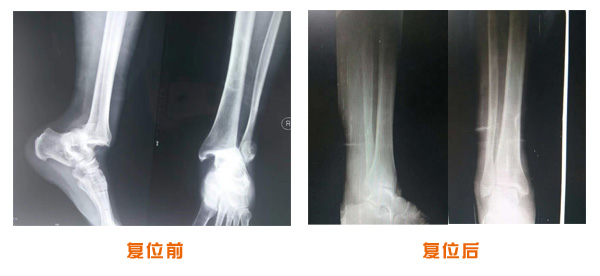

肘關(guān)節(jié)脫位骨折治療前后對比